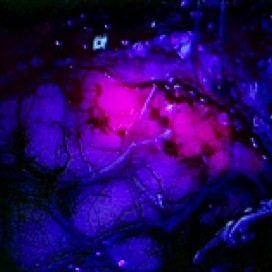

NXDC is developing Gliolan™ as an Orphan drug which enhances brain tumor visualization improving tumor removal and outcomes. https://vimeo.com/122150642

NXDC has exclusive US rights for Gliolan™ (5-aminolevulinic acid), which is approved ex-US with 58,000 patients treated. Gliolan™ is in high demand and is expected to be available in 2016 through an FDA program at leading US brain tumor centers. Gliolan™ improves tumor resection aligning strategic interests with blockbuster glioblastoma therapies. Funds on hand enable FDA approval (in 2016); a new $3M accelerates Gliolan’s market penetration